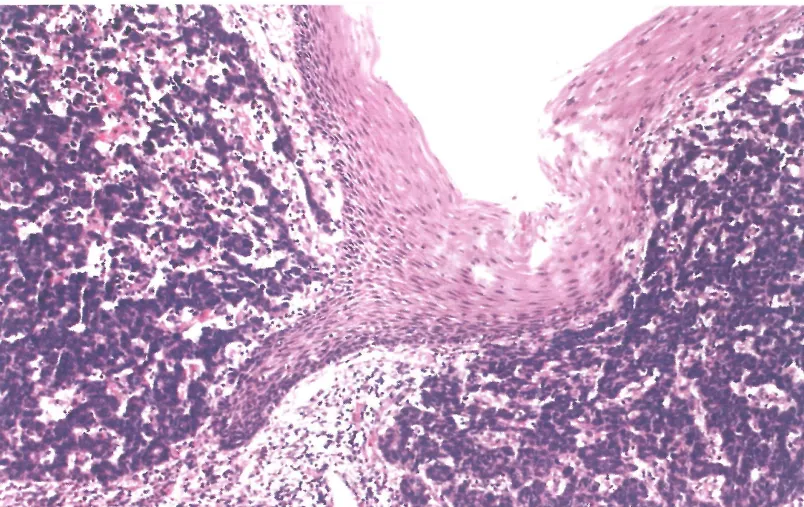

二、NEC

—这类肿瘤占所有食管NENs的90%以上

—其亚型分为小细胞NEC(SCNEC)和大细胞NEC(LCNEC)

—HE表现为实性、玫瑰花结样或栅栏样排列

—坏死常见、广泛

—核分裂象易见

—SCNEC:细胞中等偏小、N:C比值高、胞浆嗜碱性稀少、核细长且含弥散性染色质,无明显成形的核仁

—LCNECs:中等至大细胞、胞浆嗜碱性、大卵圆形核含大核仁

—IHC阳性:Syn,CgA(约60%)通常呈局灶弱表达,TTF1(约70%